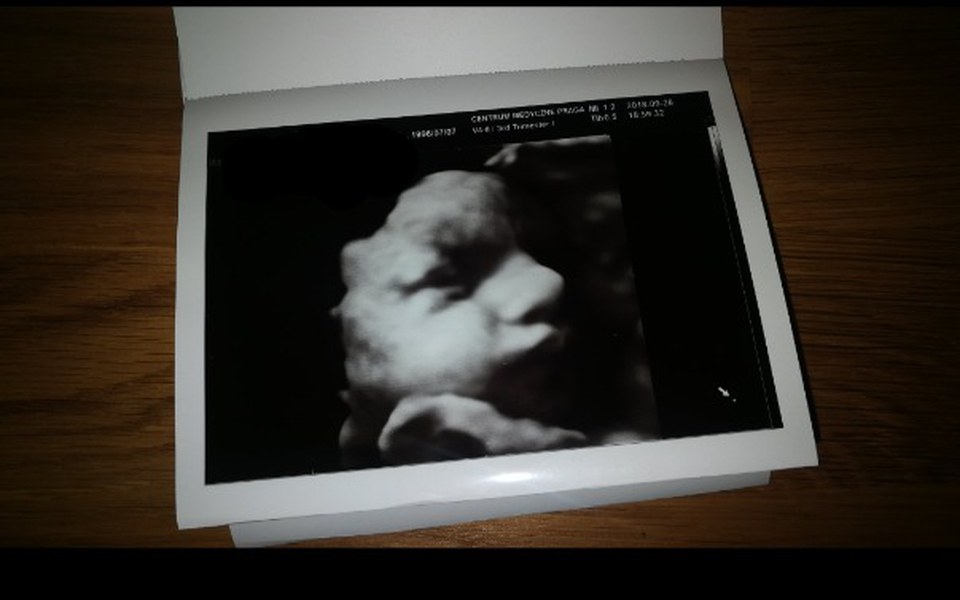

Kochani! Znajduję się obecnie w bardzo trudnej sytuacji życiowej. Pech chciał, że w momencie kiedy spotkało mnie największe szczęście w postaci dziecka, los zesłał na mnie także mnóstwo problemów. Jestem samotną matką, w momencie zajścia w ciążę wciąż się uczyłam, jestem więc bez środków do życia. Mieszkam obecnie z mamą, ale nie jest ona w stanie zapewnić nam wszystkiego. Chciałabym móc dać mojemu maleństwu szanse na dobry start. Kupić wózek oraz trochę ciuszków, kosmetyków do pielęgnacji oraz pieluszek. Wiadomo, że są to wszystko ogromne koszta.. szczególnie Ci z Was, którzy są już rodzicami rozumieją mój problem. Proszę Was o wsparcie i zrozumienie. Będę szczęśliwa z każdej kwoty, jaką uda mi się uzbierać by sprawić, że moje dziecko będzie miało cokolwiek, czego nie jestem w stanie mu zapewnić sama na ten moment.